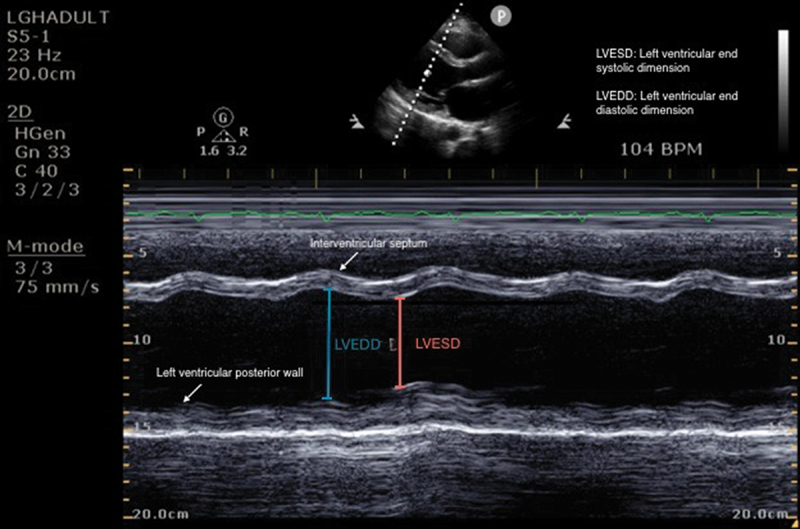

Peripartum cardiomyopathy (PPCM) is a rare cardiomyopathy marked by systolic dysfunction that presents in late pregnancy or the early postpartum period with an ejection fraction (EF) of less than 45%. Diagnosing PPCM often presents a diagnostic dilemma due to its nonspecific clinical presentation, which usually resembles physiological changes of pregnancy or peripartum pulmonary embolism. Echocardiography is frequently used as a diagnostic modality of choice with management following the GDMT guidelines and delivery. This case presents a 23-year-old patient with a delayed diagnosis of PPCM, followed by a discussion of goal-directed medical therapy (GDMT) and the benefits of early diagnosis and treatment. Common pitfalls in diagnosing PPCM are introduced to encourage clinicians to consider PPCM during late pregnancy. Currently, a new clinical trial is underway investigating the efficacy of dopamine agonists in conjunction with GDMT for treatment of peripartum cardiomyopathy.